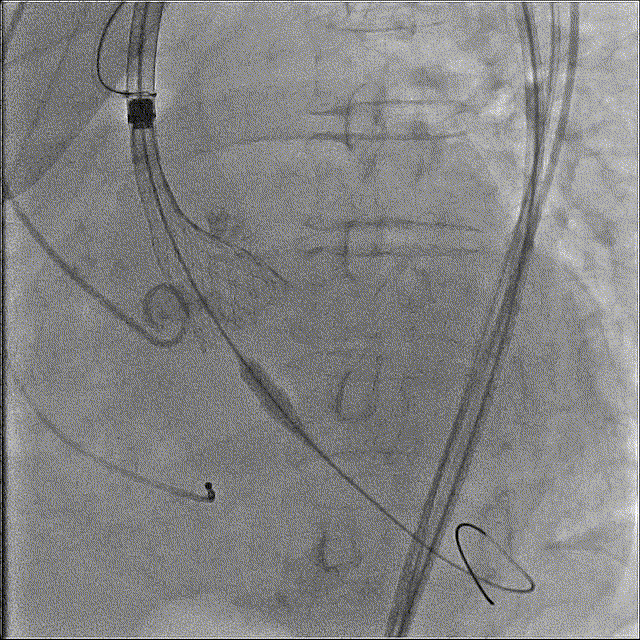

最终释放,瓣架稳定脱钩

释放后造影,可见微量反流

未见明显反流